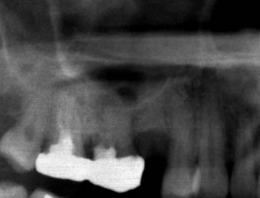

サイナスリフト症例(治療前後のCTもしくはパノラマ写真)

↓

↓